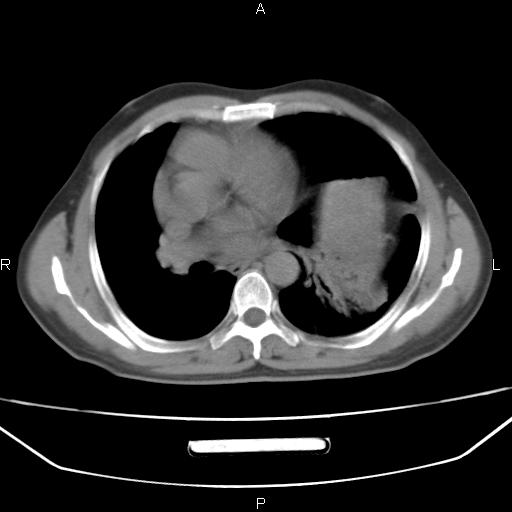

患者,男。50岁。近几日有咳嗽症状,无其他不适,既往病史无,考虑膈疝。请前辈们看看指导指导。

膈膨升,左下肺通气不良,膈肌好像还完整。

考虑左侧膈疝。

左侧膈疝。

符合隔膨升,膈肌较完整。